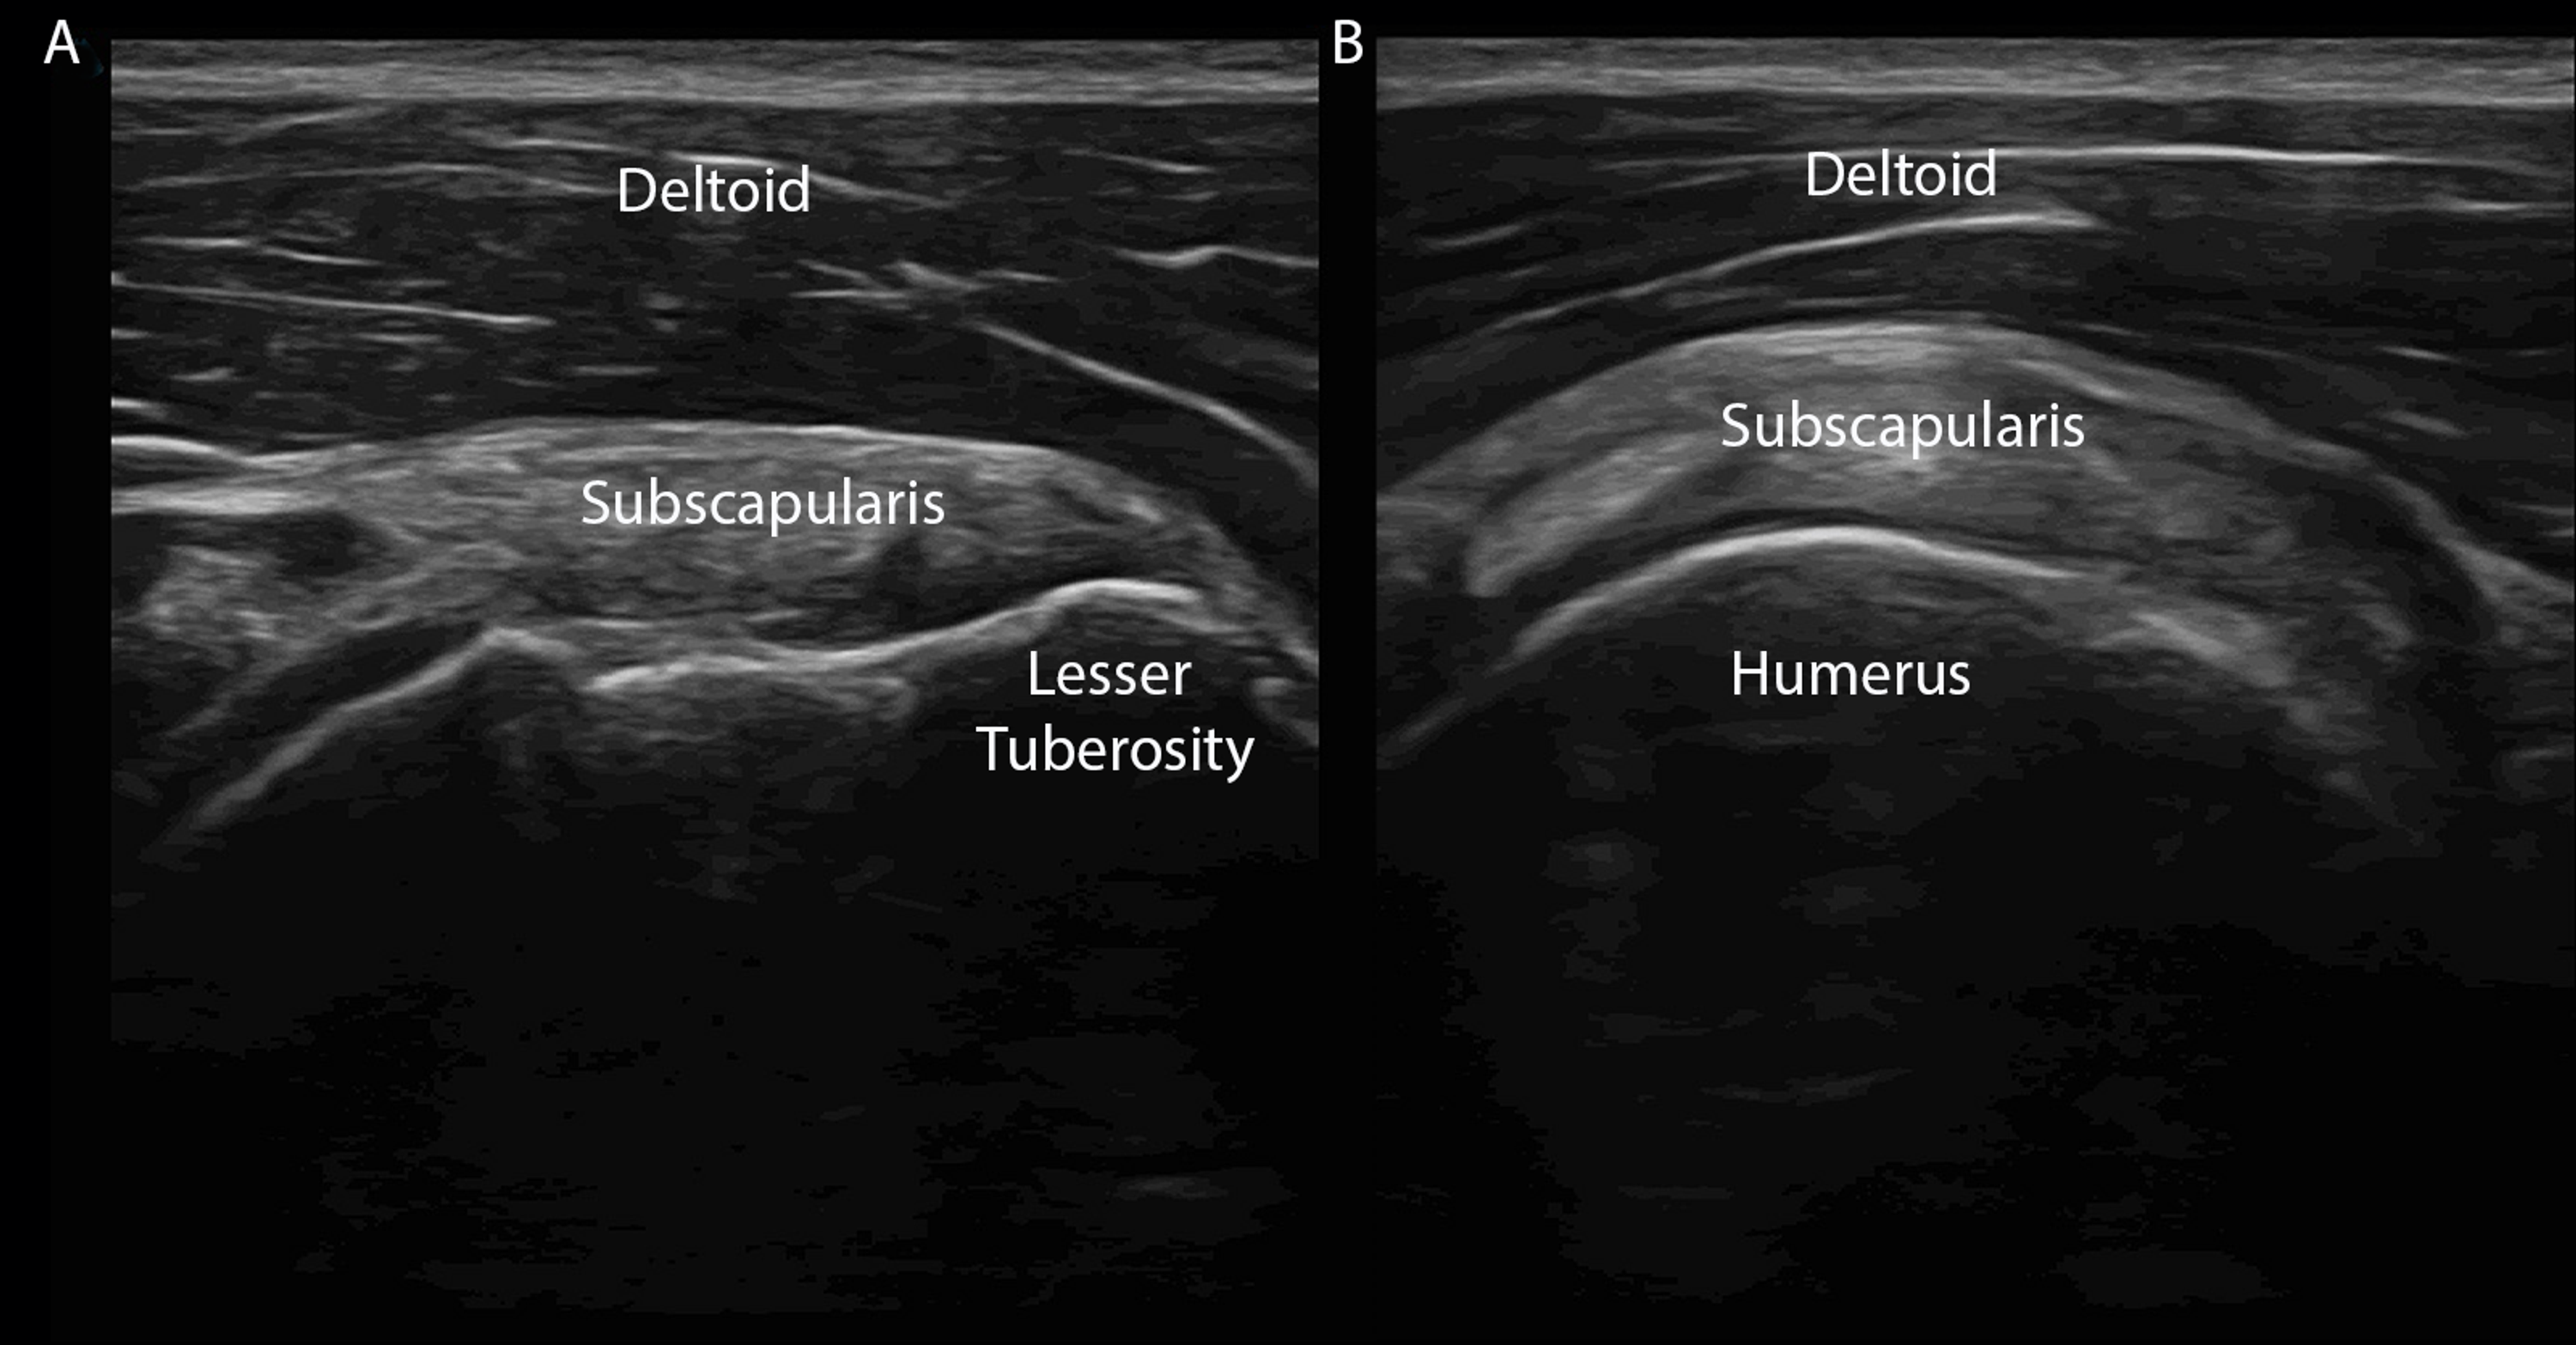

Complete rotator cuff tear (A) high frequency longaxis ultrasound of

Complete rotator cuff tear (A) high frequency longaxis ultrasound of Ultrasound Shoulder Rotator Cuff Tear Diagnostic accuracy for rotator cuff tear and biceps tendon pathology. Ultrasound of the shoulder is a fast, relatively cheap, and dynamic way to examine the rotator cuff and is particularly useful in. Accordingly, the current study was conducted to evaluate the diagnostic accuracy of ultrasound for rotator cuff disorders in patients. The society of radiologists in ultrasound convened a panel. Ultrasound Shoulder Rotator Cuff Tear.